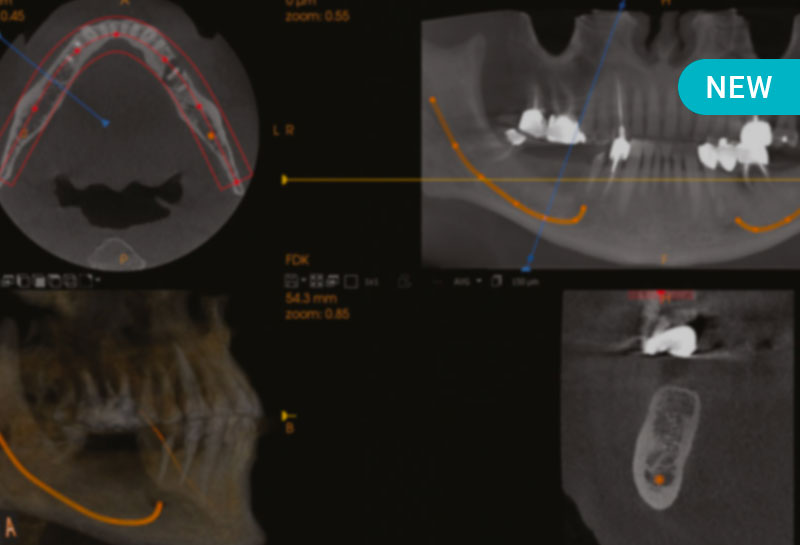

L’imagerie Cone Beam (CBCT) est devenue un outil central en pratique bucco-dentaire, en particulier pour la planification, la sécurisation et l’optimisation de prises en charge complexes (endodontie, implantologie, chirurgie, traumatologie, orthodontie…). Afin de garantir la sécurité du patient et la pertinence des décisions cliniques, son utilisation doit toutefois respecter un cadre rigoureux, fondé sur la justification de l’indication, les principes de radioprotection, l’optimisation de l’examen, la maîtrise de l’interprétation des images et enfin la capacité à produire un compte rendu conforme et sécurisant.

- Analyser de façon systématique et sécurisée un examen CBCT, en distinguant structures normales, variantes et anomalies, et en repérant les pièges d’interprétation.

- Adapter l’indication du CBCT aux principales situations cliniques (endodontie, implantologie, orthodontie, chirurgie, traumatologie…) en évaluant sa valeur ajoutée diagnostique et thérapeutique.

Module 5 – Lecture d’images : densités et pièges

- Analyse des images Cone Beam en distinguant les structures anatomiques normales des anomalies pathologiques

- Identification des pièges d’interprétation les plus fréquents afin de sécuriser l’analyse diagnostique et limiter les erreurs

Module 6 – Approche par spécialité : indications et limites

- Adaptation de l’utilisation du Cone Beam aux spécificités cliniques des différentes disciplines odontologiques

- Analyse des indications pertinentes et des limites du Cone Beam selon les situations cliniques rencontrées.